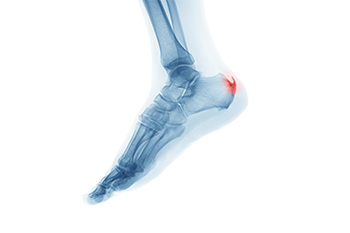

A heel spur is a bony growth that develops on the underside of the heel bone, often where the plantar fascia attaches. It typically forms over time as a response to ongoing stress or pressure on the foot. One of the main contributing factors is aging, as the tissues naturally lose elasticity and strength. Abnormal stress from repetitive activities, poor foot function, or walking patterns can place excessive strain on the heel. Carrying extra weight increases the load on the feet, which can lead to small tears in the plantar fascia. These micro-tears trigger inflammation and can encourage calcium deposits to build up, forming a spur. If you have heel pain, it is suggested that you schedule an appointment with a podiatrist who can accurately diagnose and treat heel spurs.

Heel spurs are formed by calcium deposits on the back of the foot where the heel is. This can also be caused by small fragments of bone breaking off one section of the foot, attaching onto the back of the foot. Heel spurs can also be bone growth on the back of the foot and may grow in the direction of the arch of the foot.

Older individuals usually suffer from heel spurs and pain sometimes intensifies with age. One of the main condition's spurs are related to is plantar fasciitis.

The pain associated with spurs is often because of weight placed on the feet. When someone is walking, their entire weight is concentrated on the feet. Bone spurs then have the tendency to affect other bones and tissues around the foot. As the pain continues, the feet will become tender and sensitive over time.

There are many ways to treat heel spurs. If one is suffering from heel spurs in conjunction with pain, there are several methods for healing. Medication, surgery, and herbal care are some options.